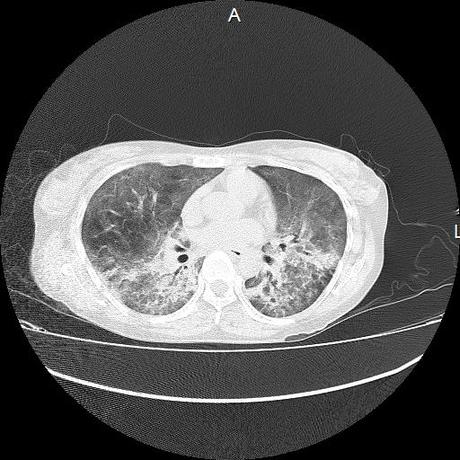

El parénquima pulmonar con areas parcheadas difusas en vidrio despulido combinadas con otras areas hipodensas de baja atenuación debidas a atrapamiento aéreo y engrosamiento intersticial y zonas de fibrosis de predominio en lóbulos medios e inferiores de ambos pulmones.

- LOS HALLAZGOS PUEDEN ESTAR EN RELACIÓN A NEUMOPATIA INTERSTICIAL PROBABLE ETIOLOGIA HIPERSENSITIVA VS AUTOINMUNE/BACTERIANA/FUNGICA.